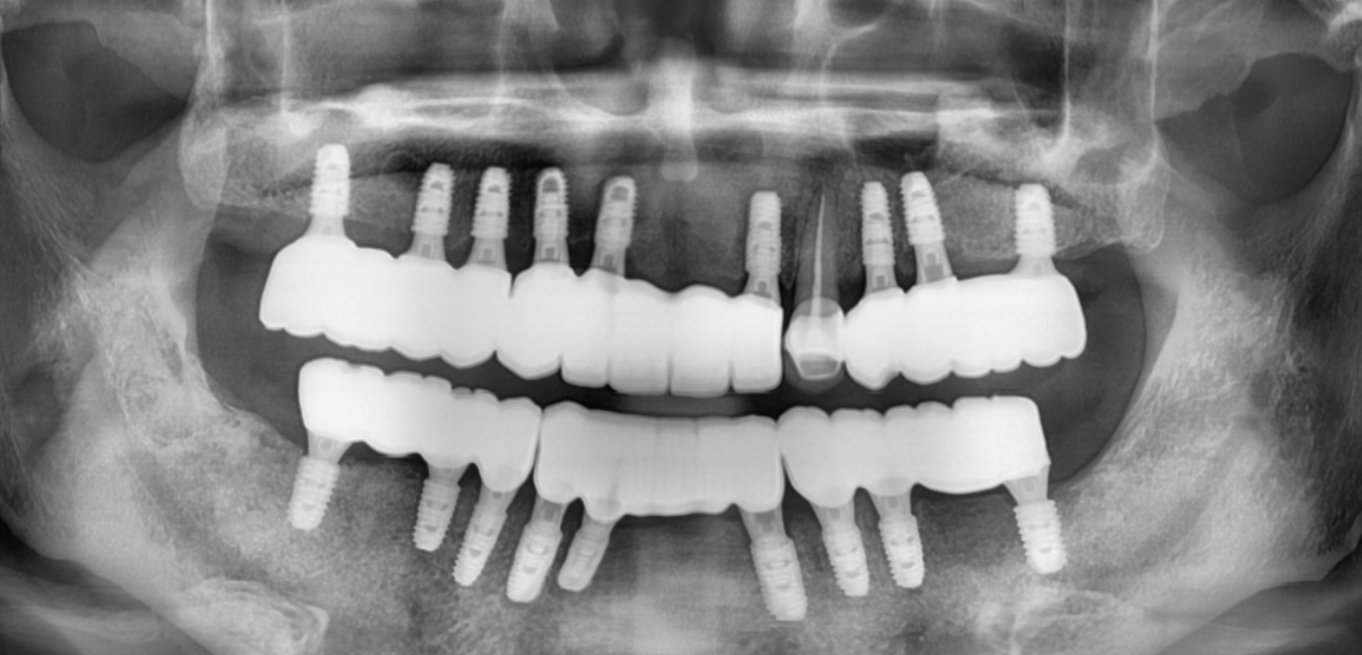

Before & After

Drag Before After

버튼을 움직여서 변화를 확인해보세요.